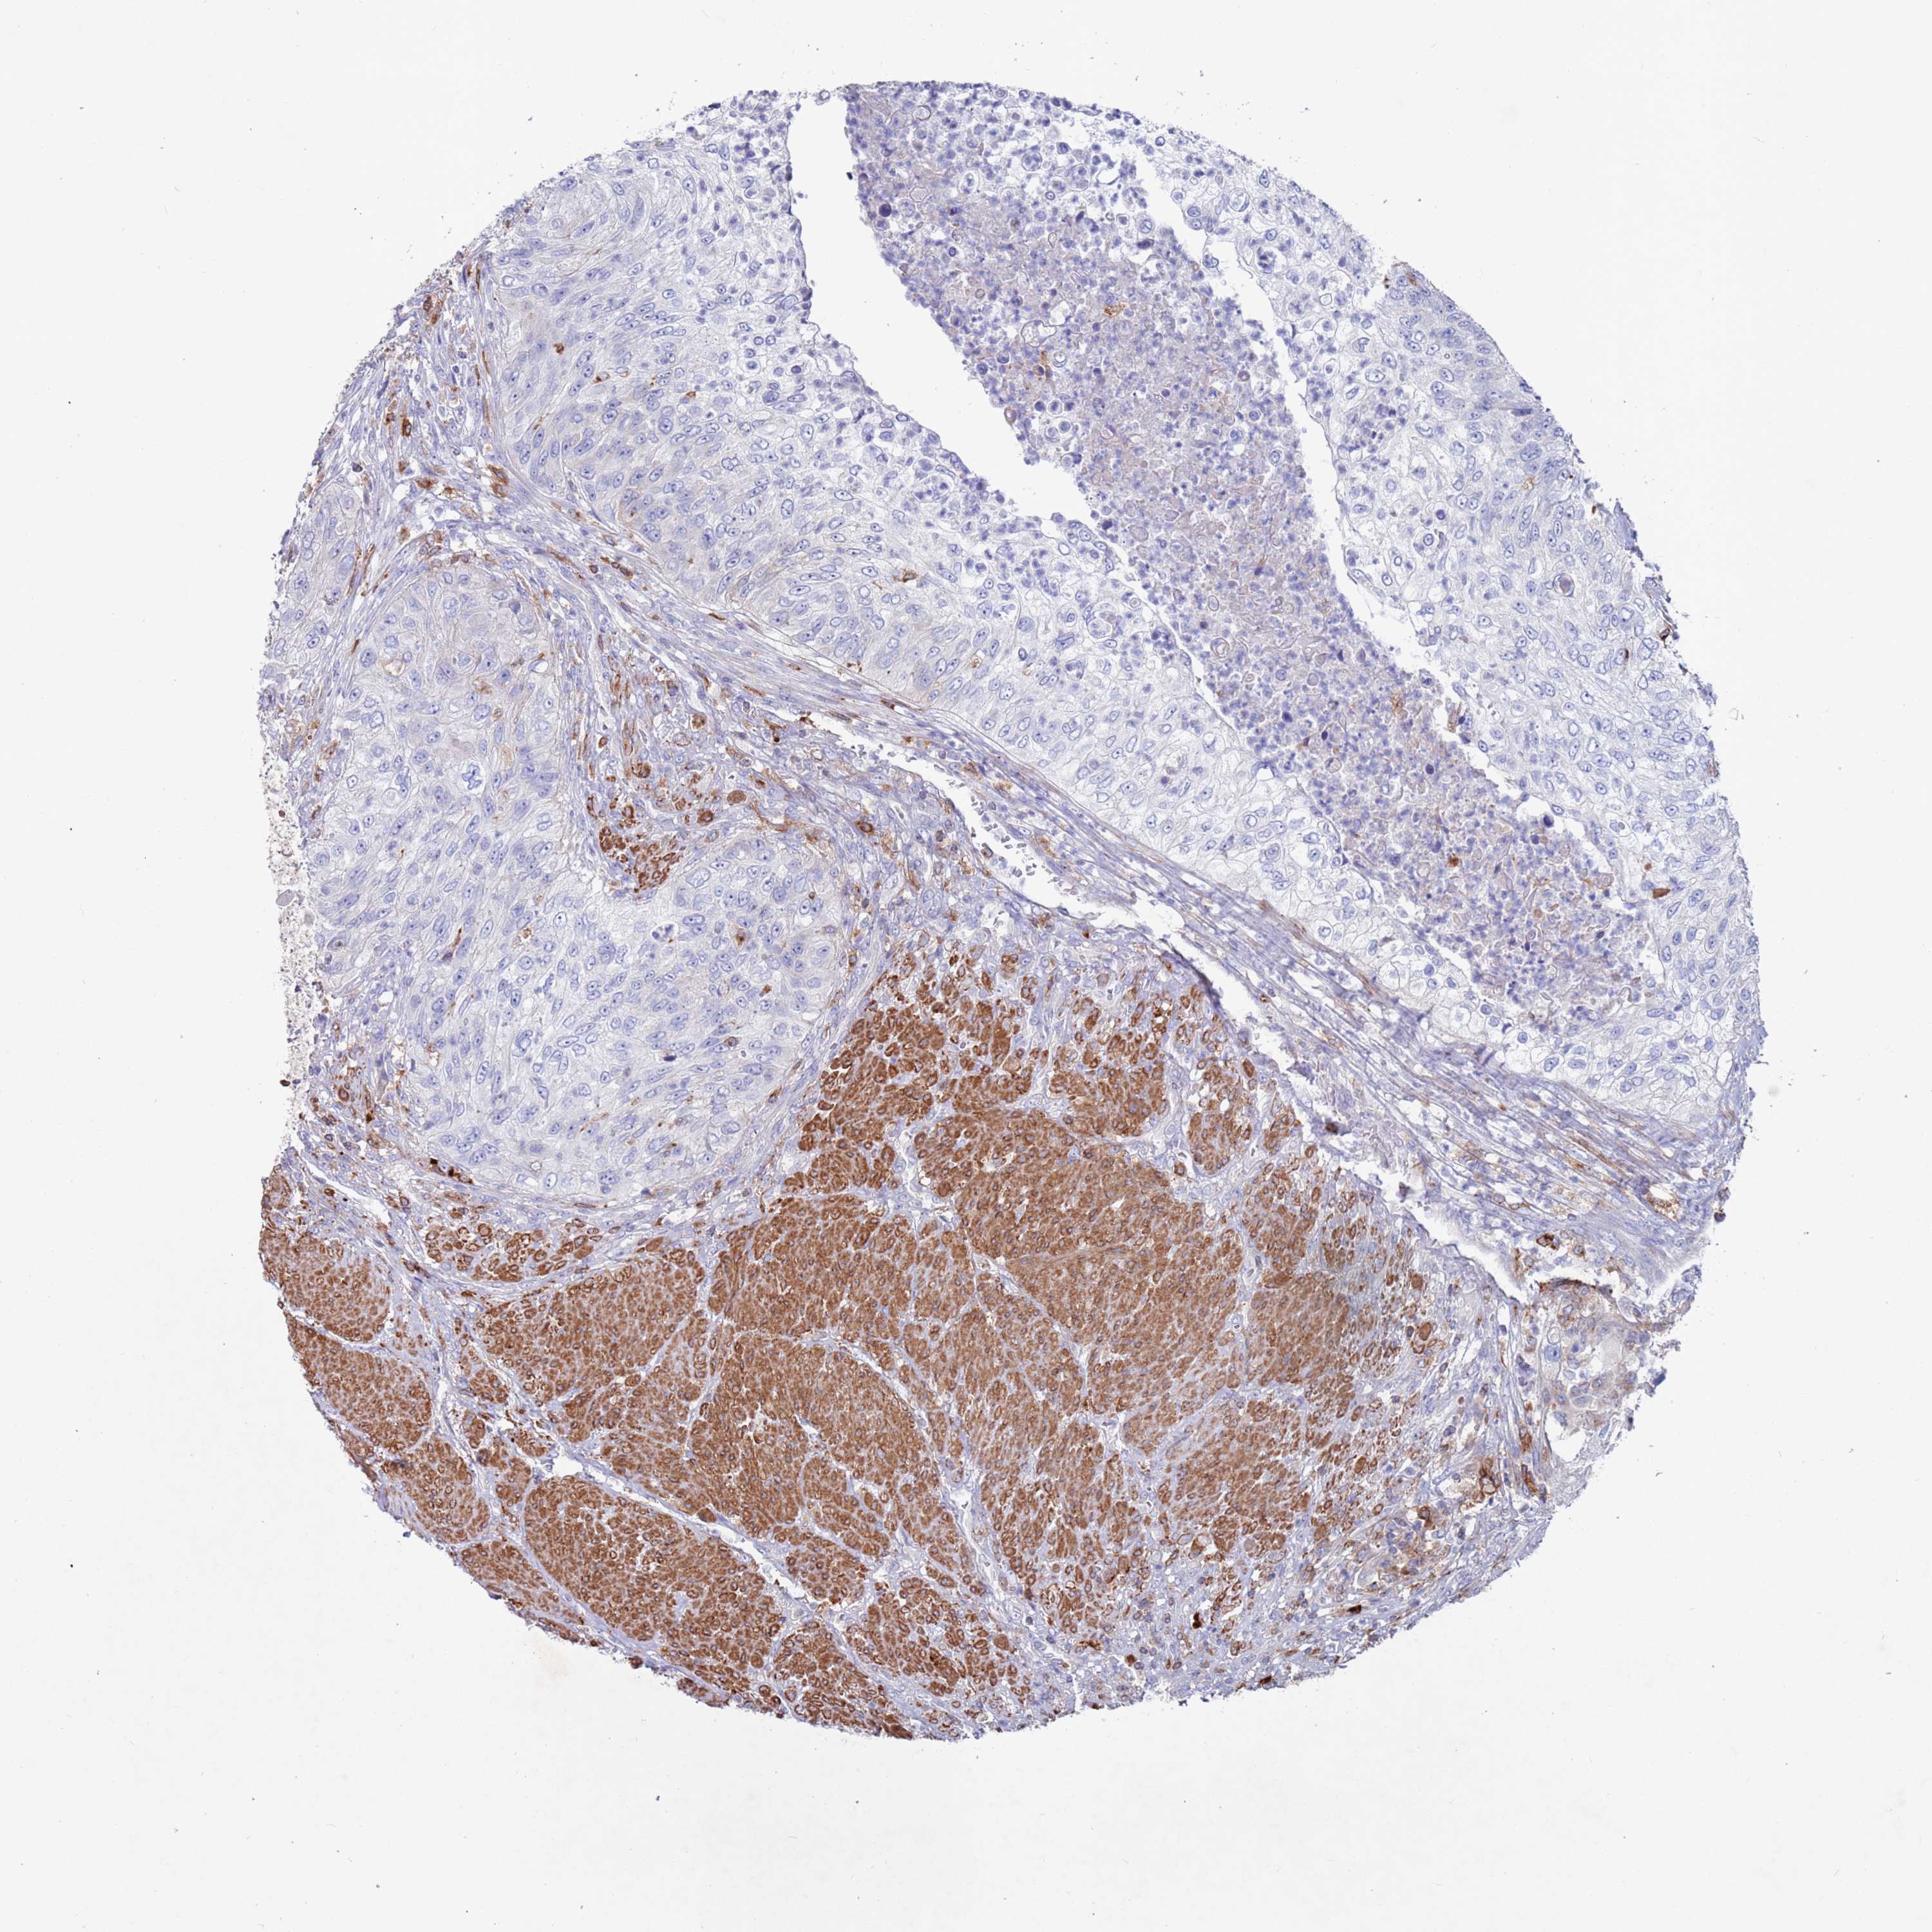

UROTHELIAL CANCER - Protein expressioni

A mouse-over function shows sample information and annotation data. Click on an image to view it in a full screen mode. Samples can be filtered based on level of antibody staining by selecting one or several of the following categories: high, medium, low and not detected. The assay and annotation is described here.

Note that samples used for immunohistochemistry by the Human Protein Atlas do not correspond to samples in the TCGA dataset.

Antibody stainingi

Antibody staining in the annotated cell types in the current human tissue is reported as not detected, low, medium, or high, based on conventional immunohistochemistry profiling in selected tissues. This score is based on the combination of the staining intensity and fraction of stained cells.

Each image is clickable and will lead to virtual microscopy that enables deeper exploration of all samples and also displays staining intensity scores, fraction scores and subcellular localization as well as patient and tissue information for each sample.

Antibody HPA041647

Antibody HPA044218

Staining

High

Medium

Low

Not detected

Intensity

Strong

Moderate

Weak

Negative

Quantity

>75%

75%-25%

<25%

None

Location

Nuclear

Cytoplasmic/membranous

Cytoplasmic/membranous,nuclear

Urothelial carcinoma, High grade

Urothelial carcinoma, Low grade